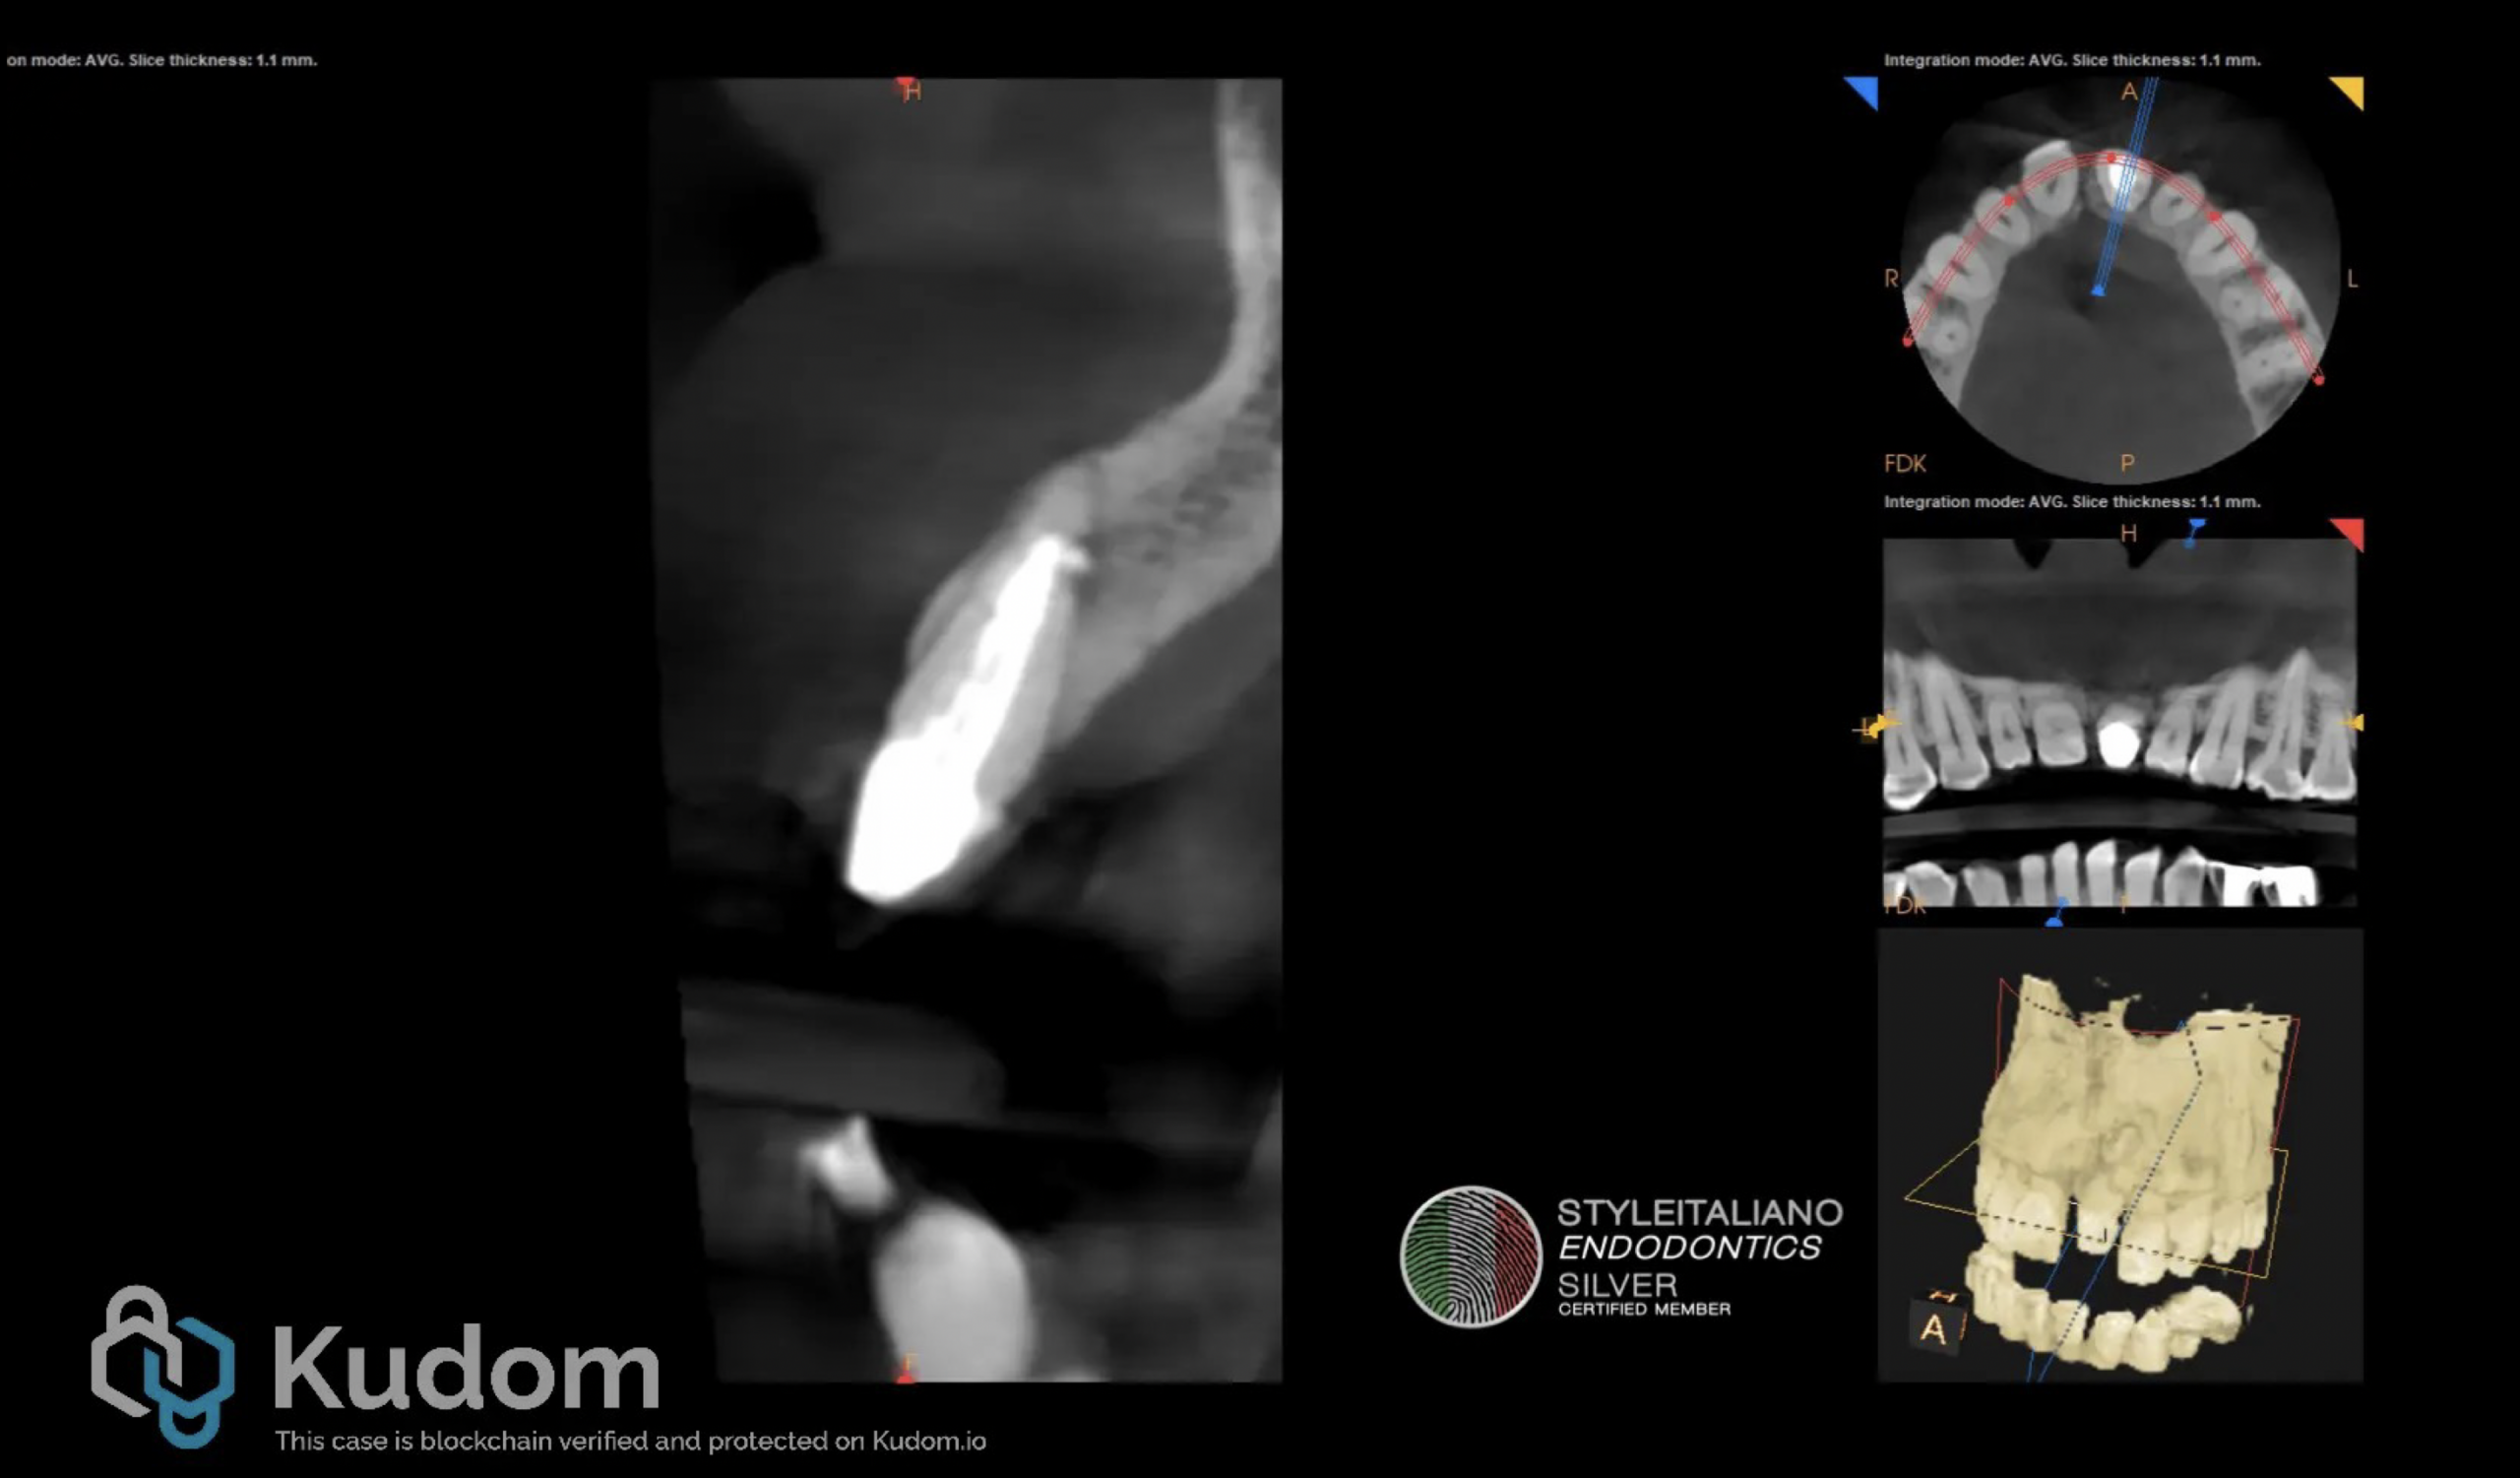

Fig. 3

The canal was sealed using mineral trioxide aggregate (MTA) apical barrier and warm gutta-percha with resin sealer as seen in Figure 3. Intracoronal sealing was done with a dual cure flowable composite resin.